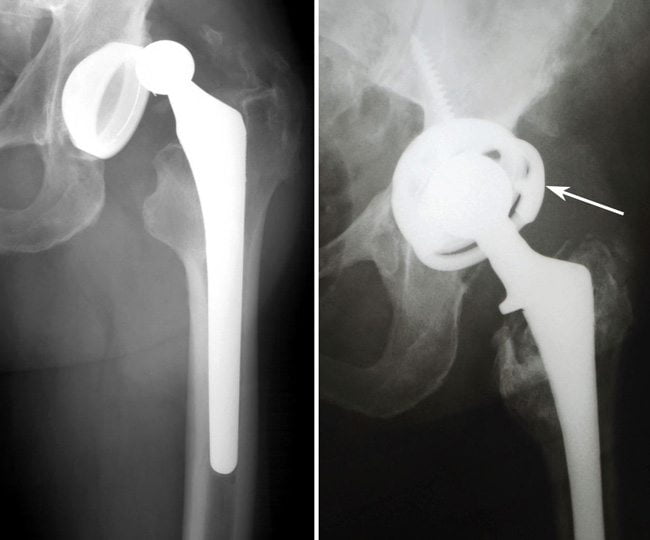

После установки искусственного тазобедренного сустава в течение 3 недель пациент находится в хирургическом стационаре. Затем реабилитация может проходить в течение месяца в специализированных центрах или в домашних условиях. Для полного восстановления ТБС требуется от 3 до 4 месяцев. На продолжительность реабилитации влияет возраст, вес пациента, тяжесть течения патологии, физическая подготовка. Немаловажен и метод хирургического вмешательства. Период восстановления несколько короче при однополюсном протезировании — замене только головки бедренной кости. Если устанавливается и искусственная вертлужная впадина, то для разработки сустава потребуется больше времени.

- протез с цементной фиксацией позволяет полностью нагружать ногу уже через 4-6 недель. При бесцементной фиксации искусственного сустава полнообъемная нагрузка возможна спустя 2 месяца.